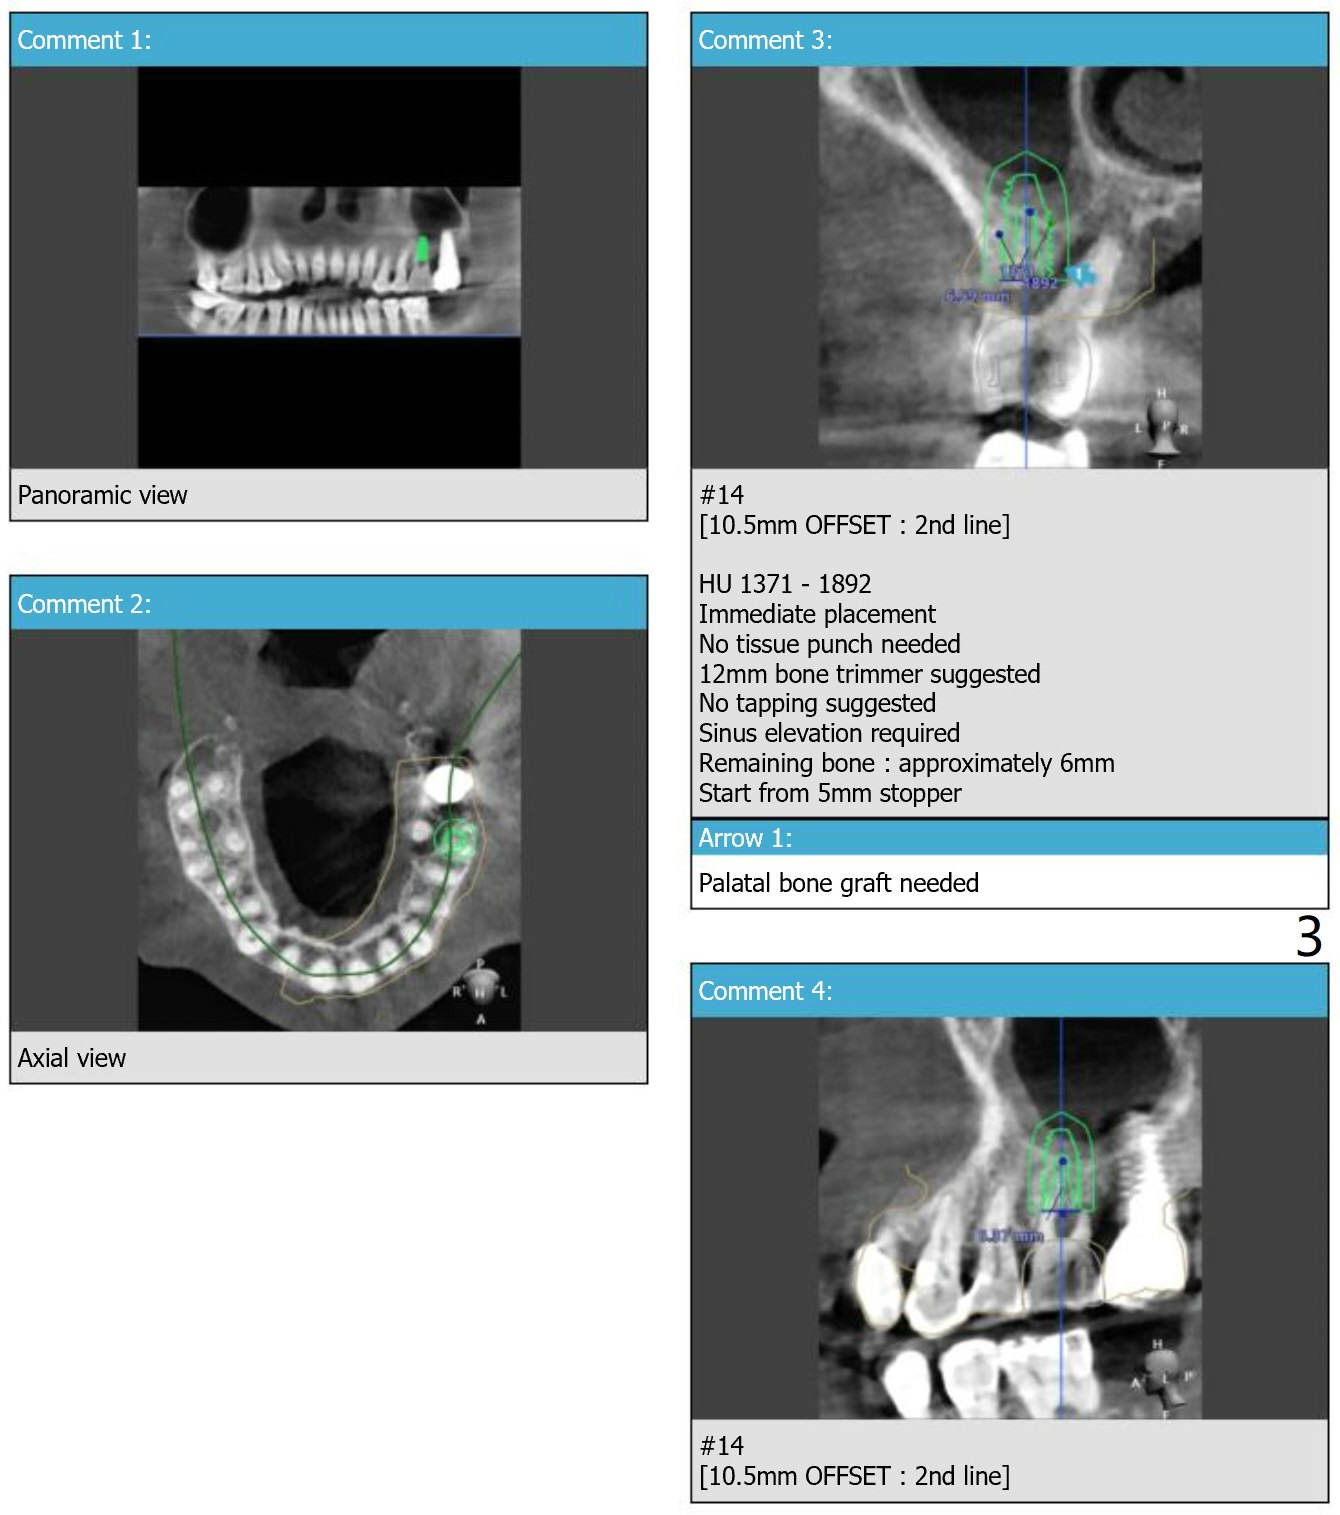

A 61-year-old woman, 2-3 PRF membranes for sinus lift and palatal wall defect repair. In fact a 5x14 mm Tatum implant will be placed to prevent screw loosening.